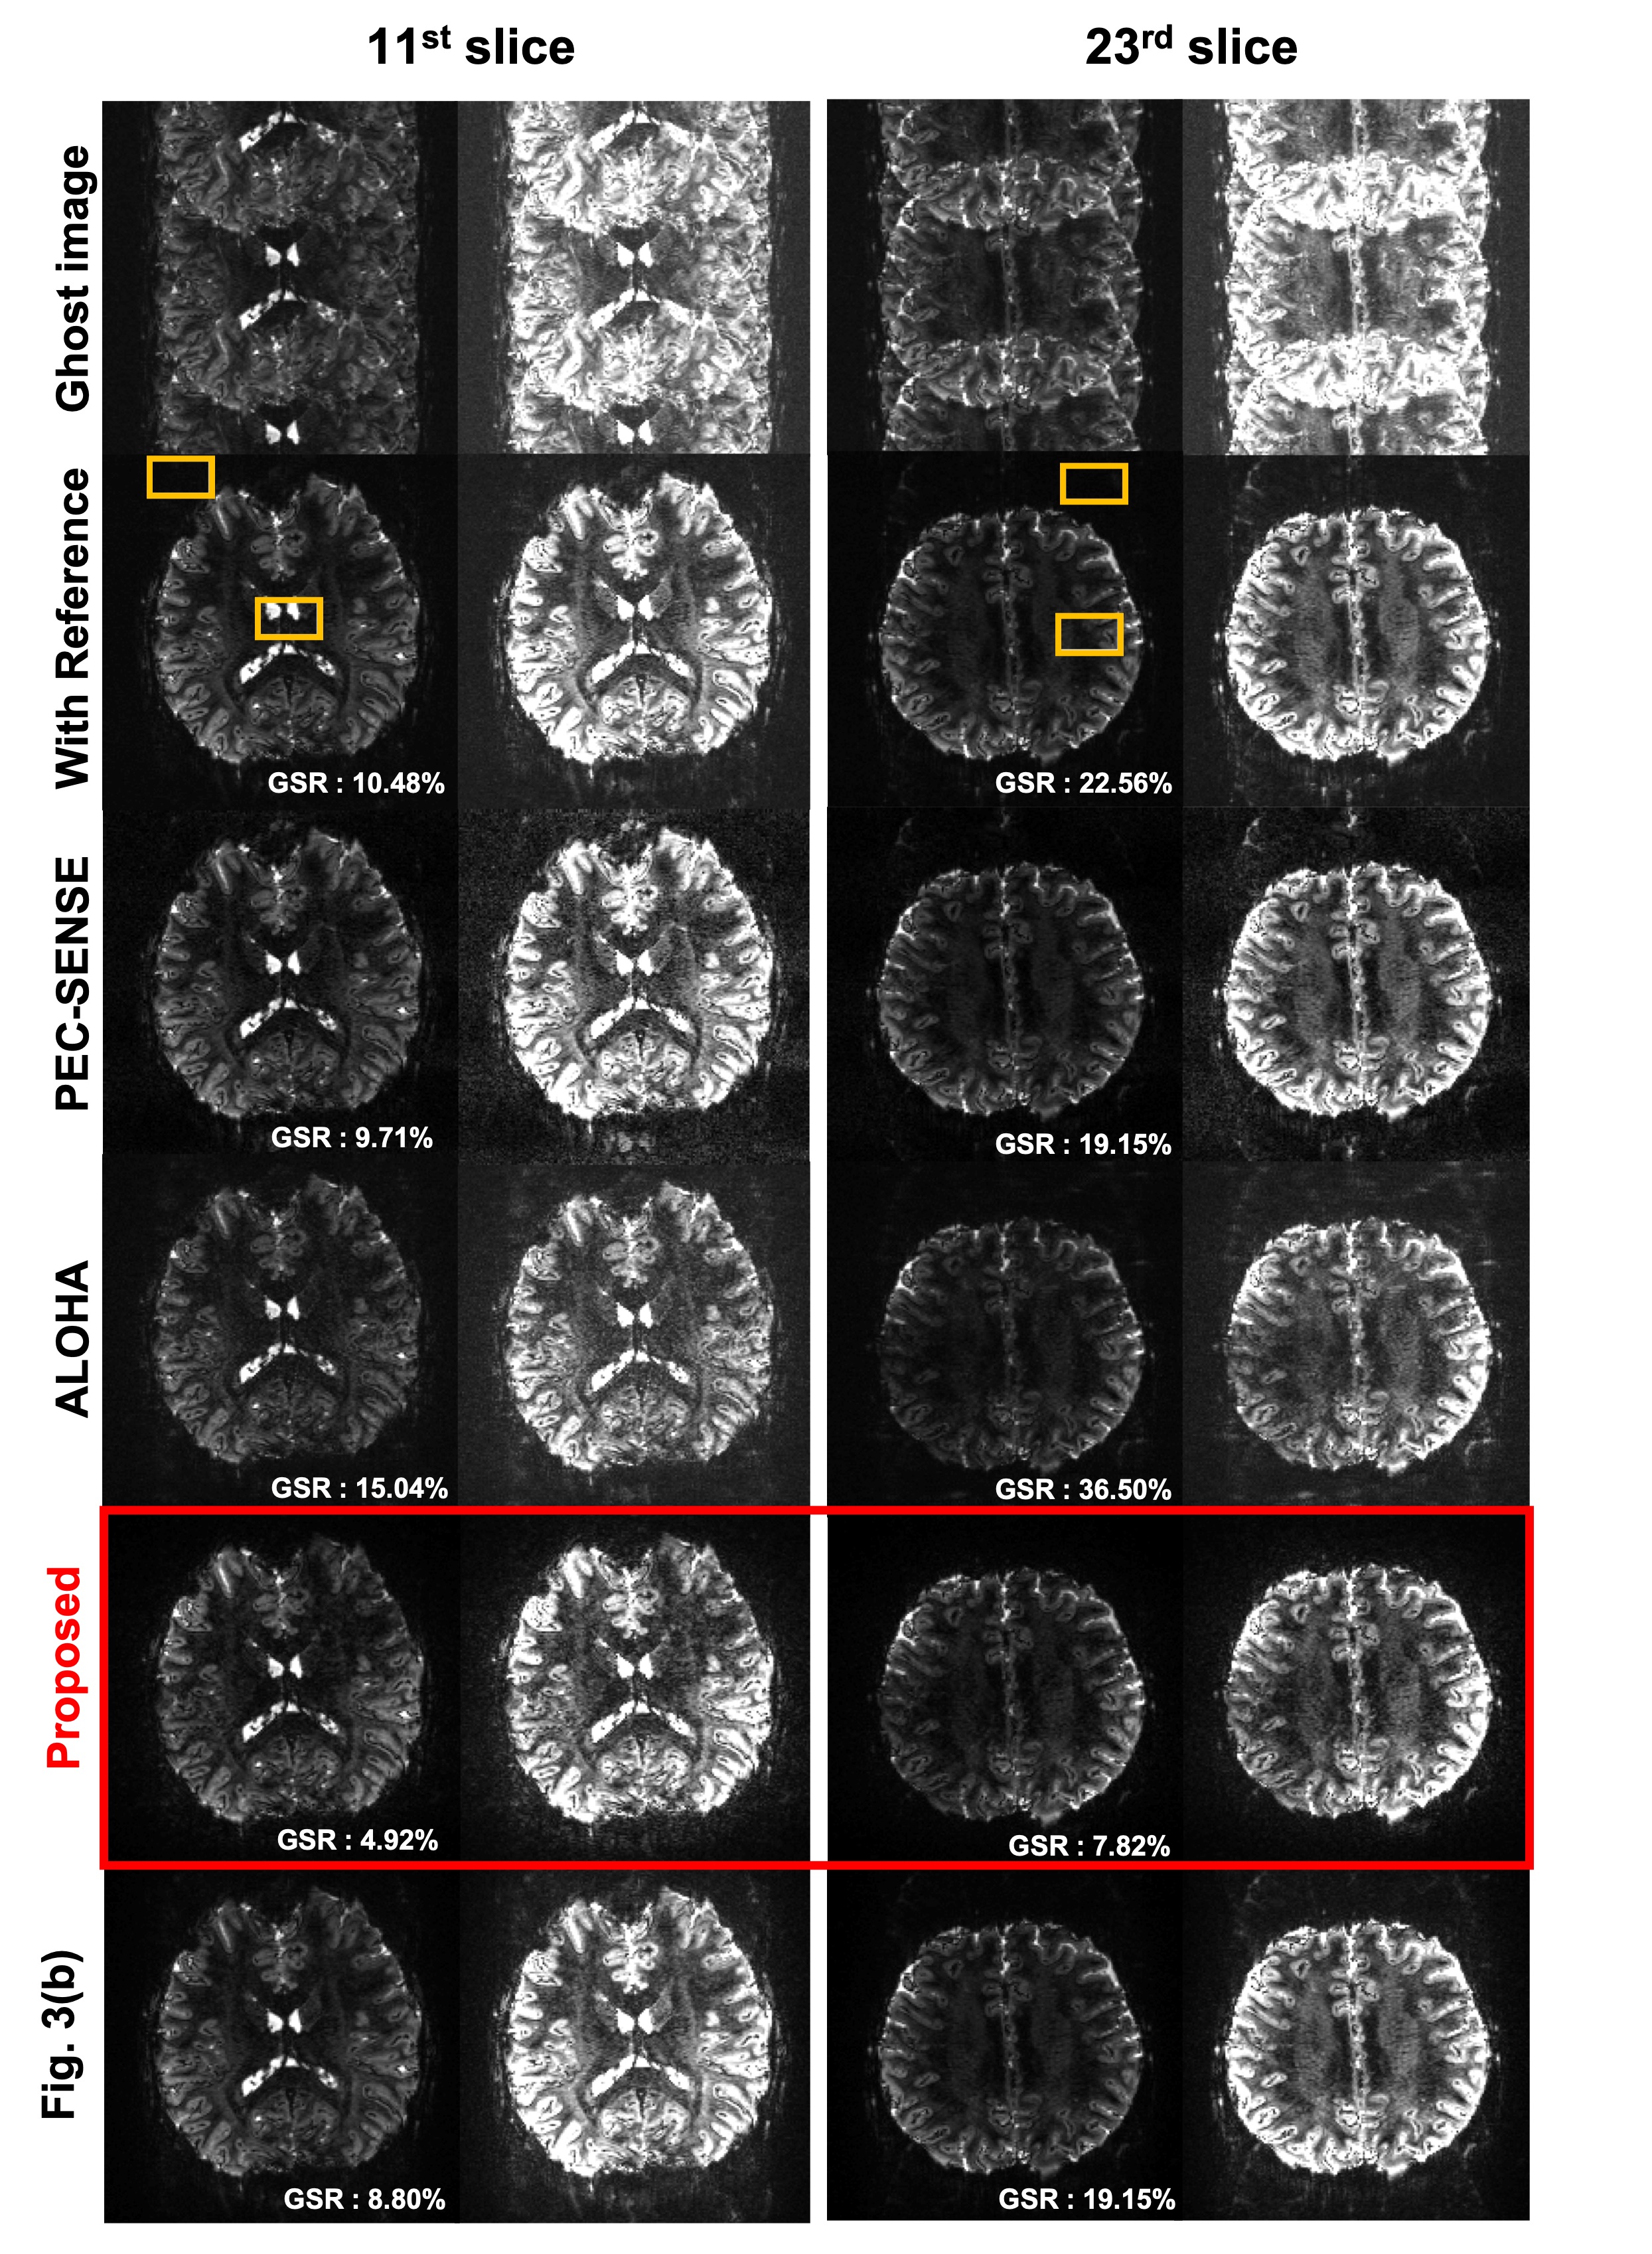

The results for 3T EPI ghost correction is shown in Fig. 5. The intensity re-scaled result images are also shown in the figure. In order to observe the remaining ghost more concisely, the image scale was re-scaled at 5 times of original intensity. The reconstruction performance of various ghost correction methods are mostly good in 3T EPI data, but slightly remaining ghost artifact can be seen in the intensity magnified images from the conventional methods. Now, Fig. 6 shows the 7T EPI ghost correction result with corresponding 5 times increase in brightness image. Most correction methods except the proposed method shows a remaining ghost artifact. Furthermore, Fig. 6 confirmed that the proposed method for accelerated EPI data (see Fig. 3(a)) can accurately correct ghost artifacts and provide visually similar results from the network in Fig. 3(b) that explicitly utilizes the GRAPPA kernel estimation steps.

To compare the result quantitatively, we calculate the ghost to signal ratio and mark ghost-to-signal ratio (GSR) value on the result figure. The GSR values corresponding to each result are calculated using regions represented by the yellow boxes and marked on the image. As shown in this result, the proposed method successfully removed ghost artifacts and shows the lowest GSR value. Although the performance of the PEC-SENSE which uses the parallel imaging information is better than the other existing methods, the GSR value was higher than the proposed method. Moreover, the proposed method using Fig. 3(a) provides much smaller GSR values than the network training using Fig. 3(b).